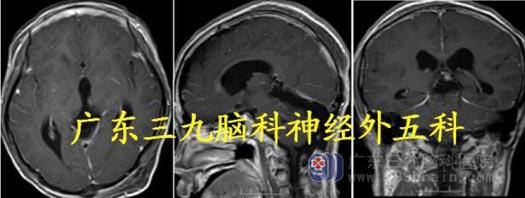

头颅MR:前额部右侧示团块状长T1 稍长T2 异常信号,FLAIR 序列呈稍高信号,病灶内可见小血管影;增强后明显强化,范围约65.9mm×47.6mm×50.6mm,右侧海绵窦区血管受压增粗、瘤灶边缘可疑脑膜尾征,并局部凸入嗅束区,考虑脑膜瘤可能性大;待排HPC/SFT。

术后复查MR 显示肿瘤切除彻底,病理:孤立性纤维性肿瘤/血管周细胞瘤,G3(相当

于间变性血管周细胞瘤),WHO III 级。